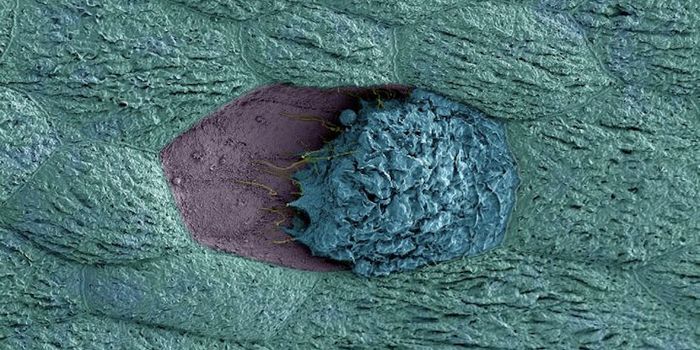

JUN 08, 2018MicrobiologyThe S. aureus pathogen doesn't only invade bone, it uses it as a snack.

MAR 08, 2015Health & MedicineIs it love or a diarrheal parasite? In this Valentine's-appropriate image, it's the parasite. Caught on scanning electro ...